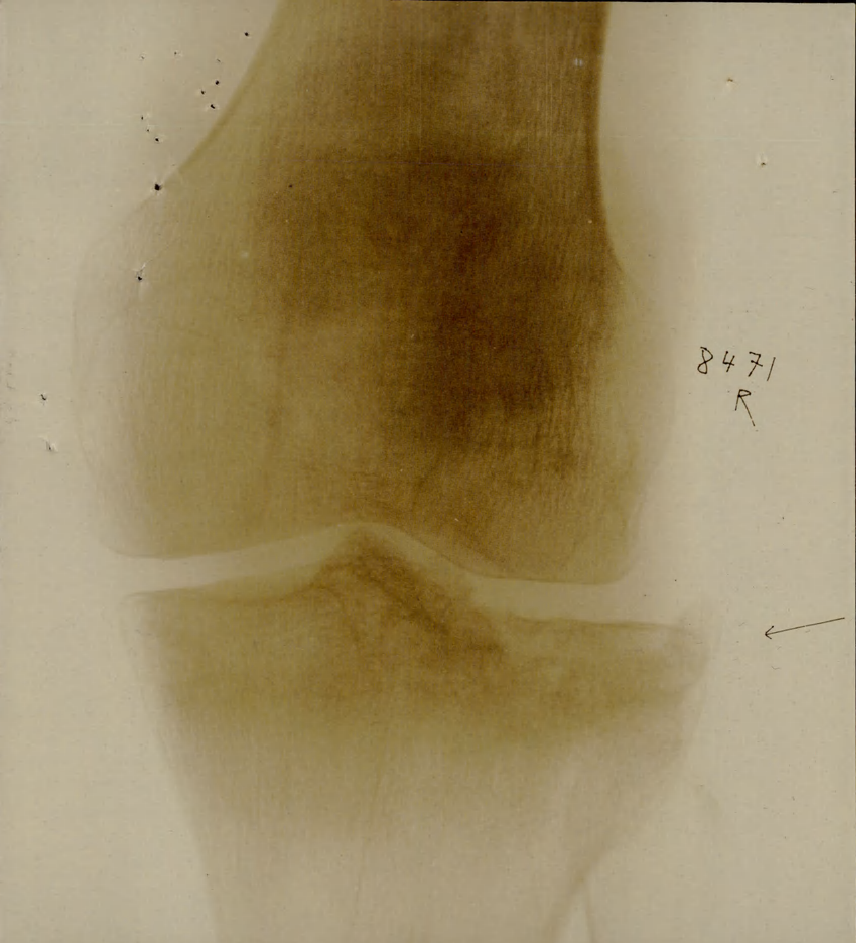

153rd Wellington: Trade listed as Farmer. DOB 13-11-96, born West Garafraxa. 6 foot 1 inch. Brown eyes, dark brown hair. Methodist. NOK Thomas Conlin, father. Elizabeth Conlin, mother. Brother to 928189 Harry Ross Conlin. Enlisted Fergus 18-1-16 (age 19 years 1 month). On 153rd Battalion Nominal Roll as published Guelph Mercury 1-12-16. Embarked with the 153rd Halifax N.S. SS Olympic 29-4-17. Arrived Liverpool 7-5-17. Assigned 25th Reserve for Training and Administration. Taken on Strength 18th Battalion 18-12-17. Hospitalized 10-1-18, German Measles. Returned to Canadian Reinforcements 27-2-18. Taken on Strength 18th Battalion in the field 8-8-18. Wounded 28-8-18, GSW right knee and tibia. Globe & Mail Casualty List 8-9-18 under Infantry reports wounded. Returned to Canada SS Aquitania 25-5-19. Demobilized Toronto 27-5-19. Died 1982 buried Belsyde Cemetery Fergus, headstone photo courtesy B. Gilbert. Photo ph15588 courtesy Wellington County Museum & Archives.